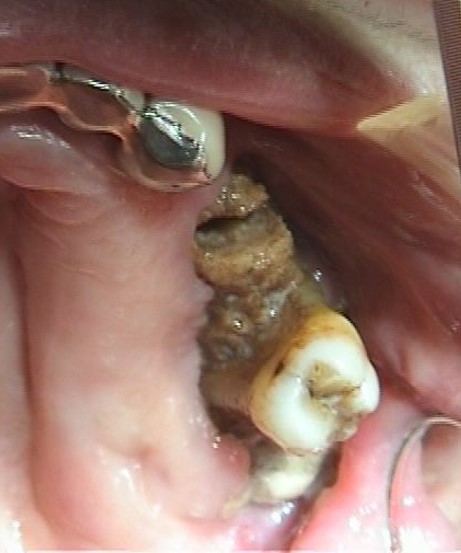

Clinica:

Segno clinico maggiore:

- Esposizione osso necrotico (Cavo orale)

Segno clinico minore:

- Alitosi

- Ascesso odontogeno

- Asimmetria mandibolare

- Dolore

- Fistola (intra ed extra orale)

- Fuoriuscita liquido dal naso

- Mobilità dentale

- Secrezioni purulente

- Segno di Vincent

- Trisma

- Tumefazione tessuti molli

caso di osteonecrosi mandibolare inferiore di sinistra